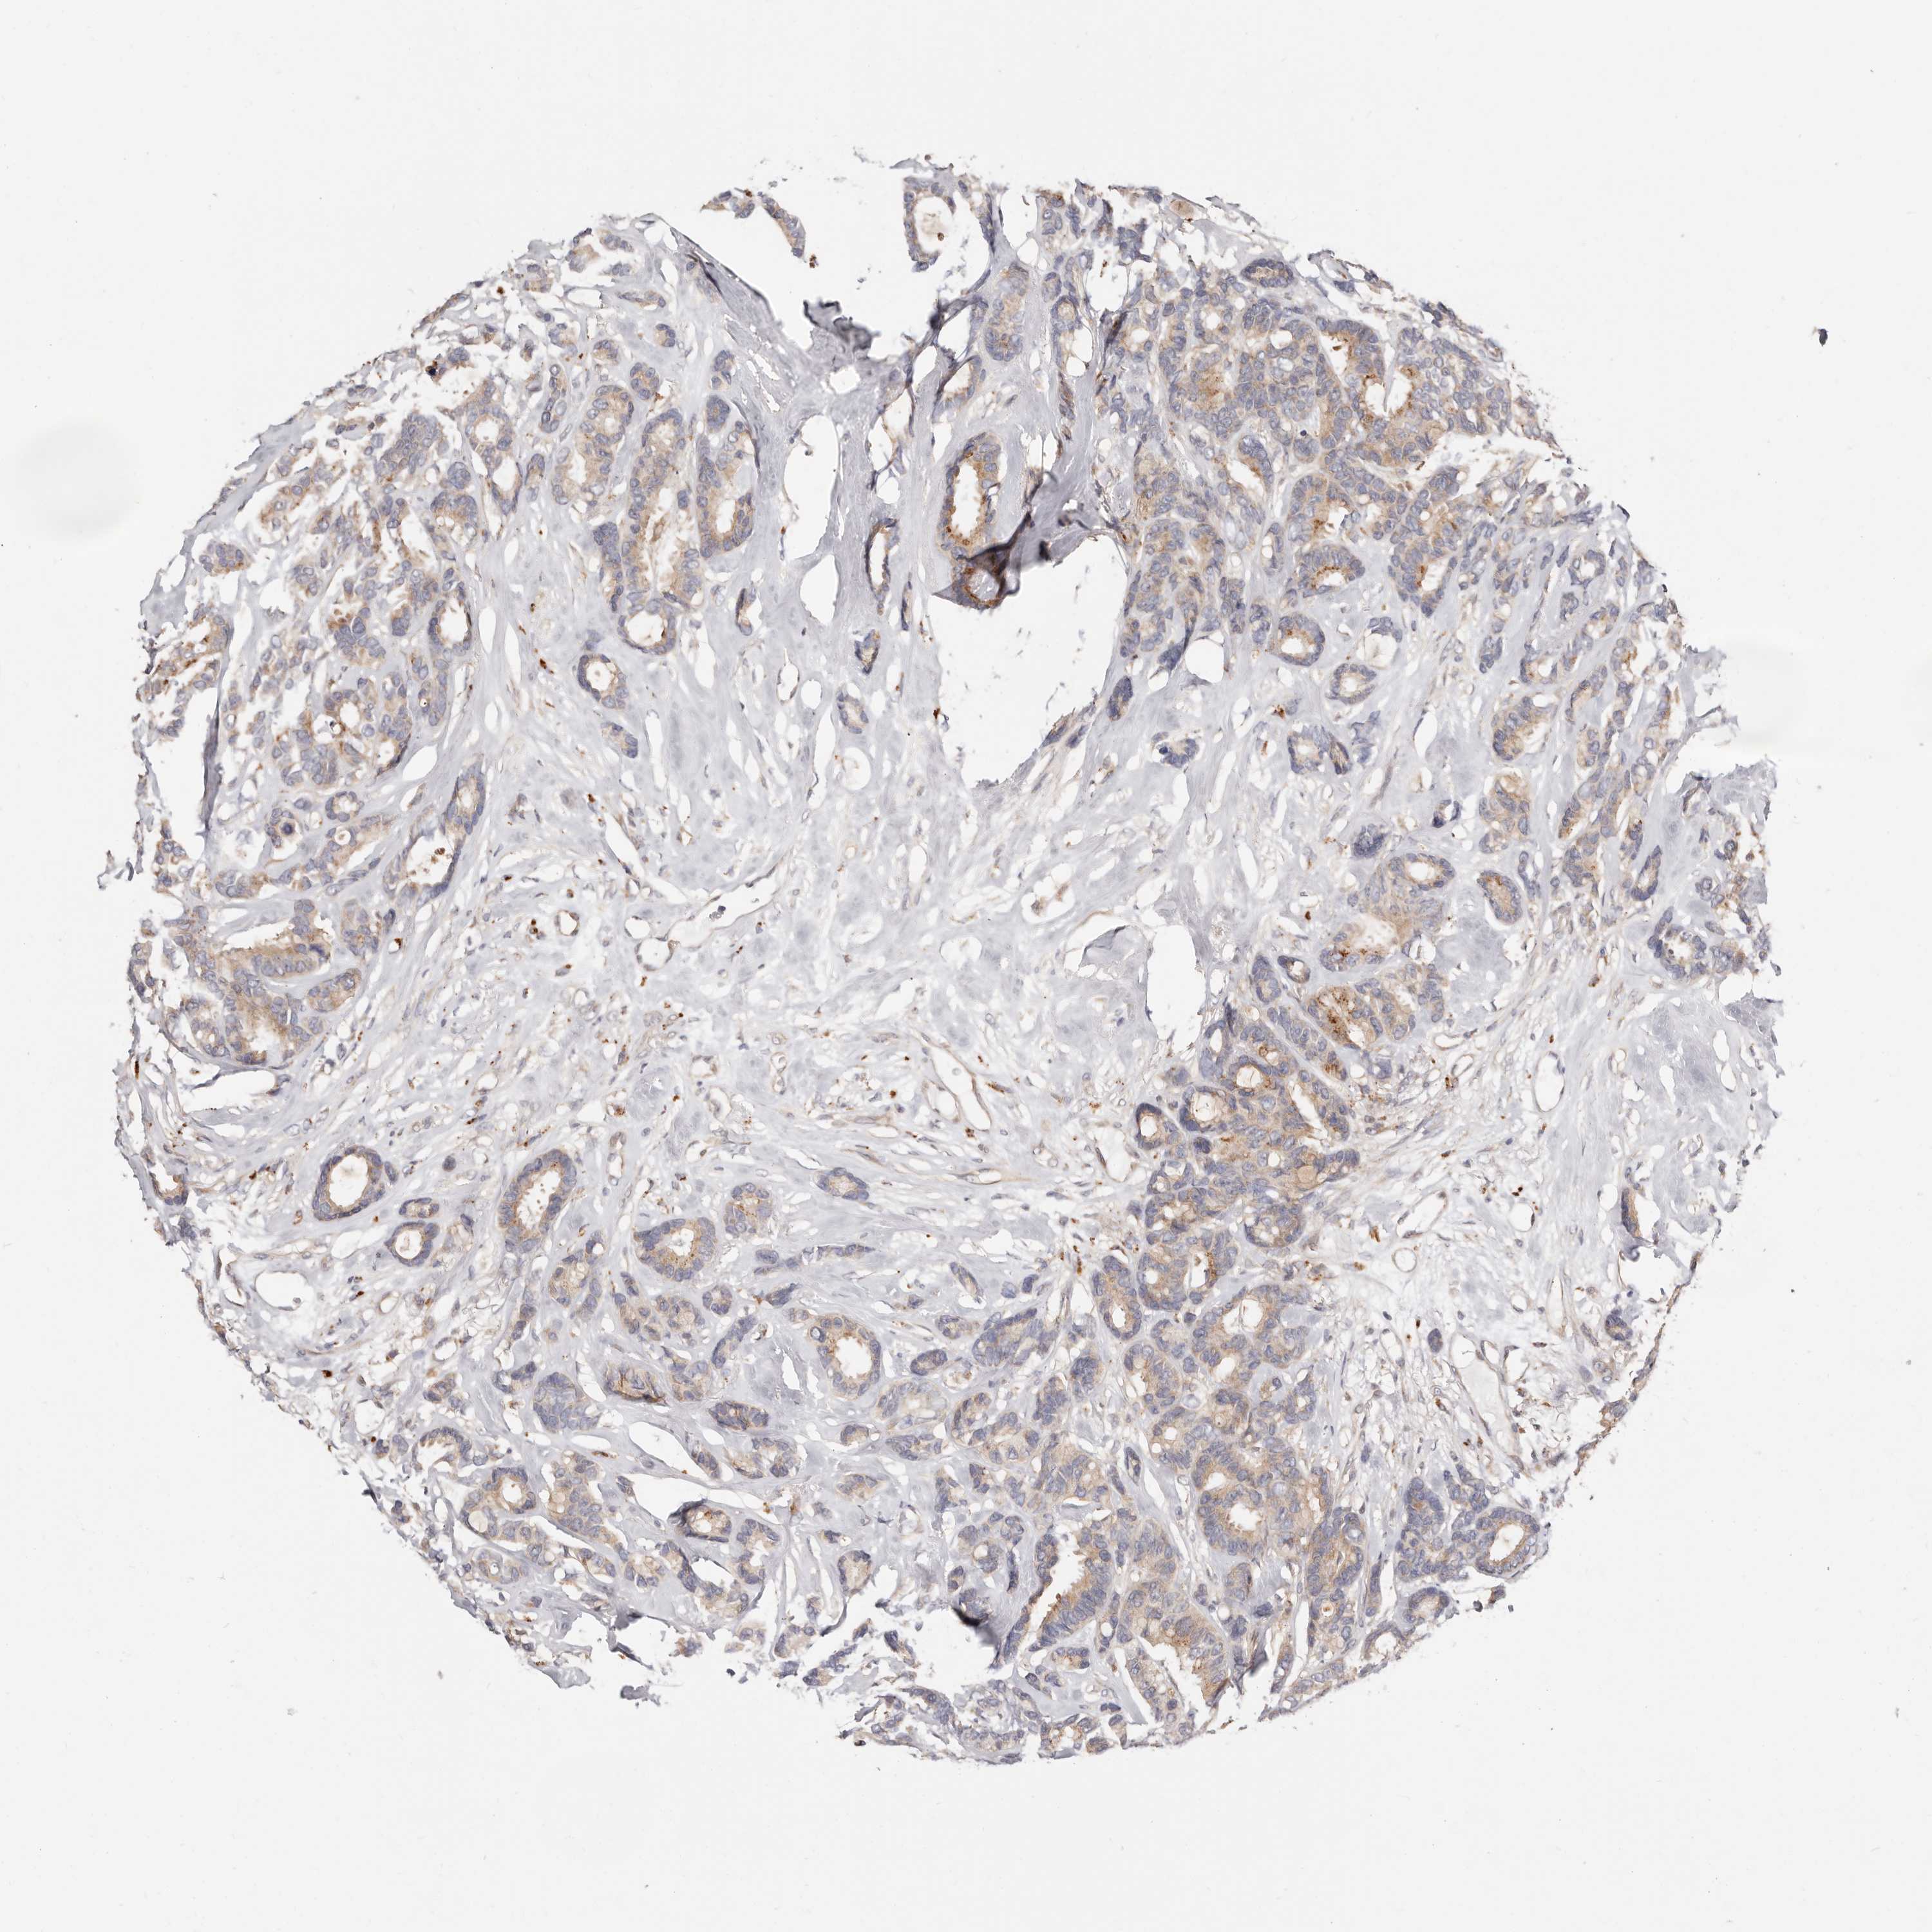

CANCER BREAST CANCER Show tissue menu

BRCA TCGA BRCA VALIDATION PROTEIN EXPRESSION

ANTIBODIES

AND

VALIDATION